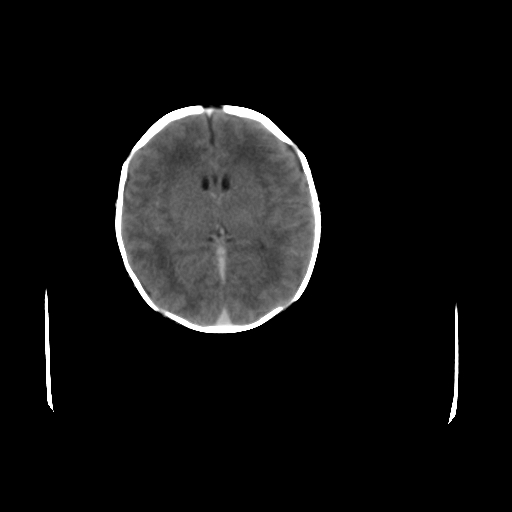

男,12天,自然分娩,其母发现右顶部头皮包块逐渐增大。

右顶部头皮血肿,可能是产道挤压所致。以后会慢慢恢复。

鉴别:骨膜下血肿,一般为产伤,应用产钳之类的吧

疑问:患儿脑白质密度比较低,基底节区密度比较高,类似于“双圈征”脑沟密度也偏高。该婴儿可有别的异常吗?反射正常吗?评分能达到5分吗?如果正常,就随诊观察吧。不正常要考虑到缺血缺氧性脑病。